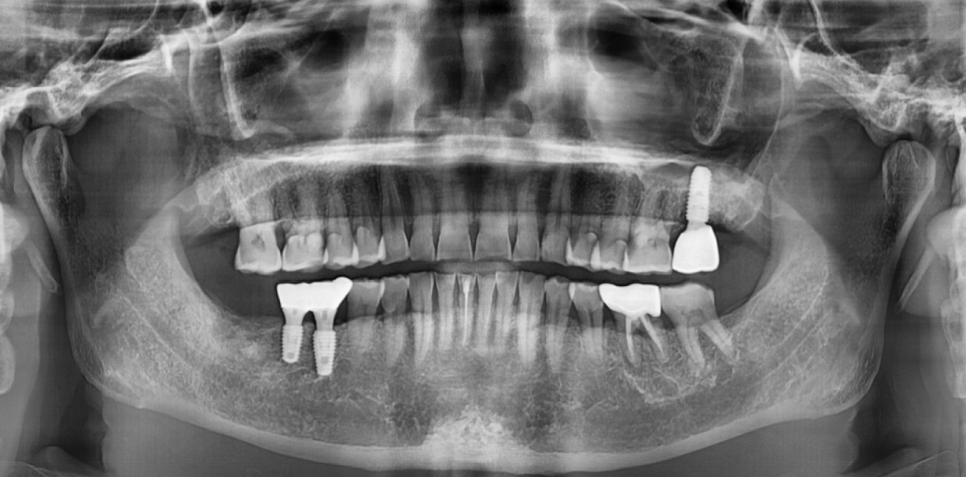

망월동 치과에서는

애초에 보철을 잘못 만들지 않기 위하여

디지털 기술을 적극 활용합니다.

구강 상태를 최대한 재현하여

애초에 잘못 만들 수 있는

가능성을 조금이라도 줄여주는 것이죠~~